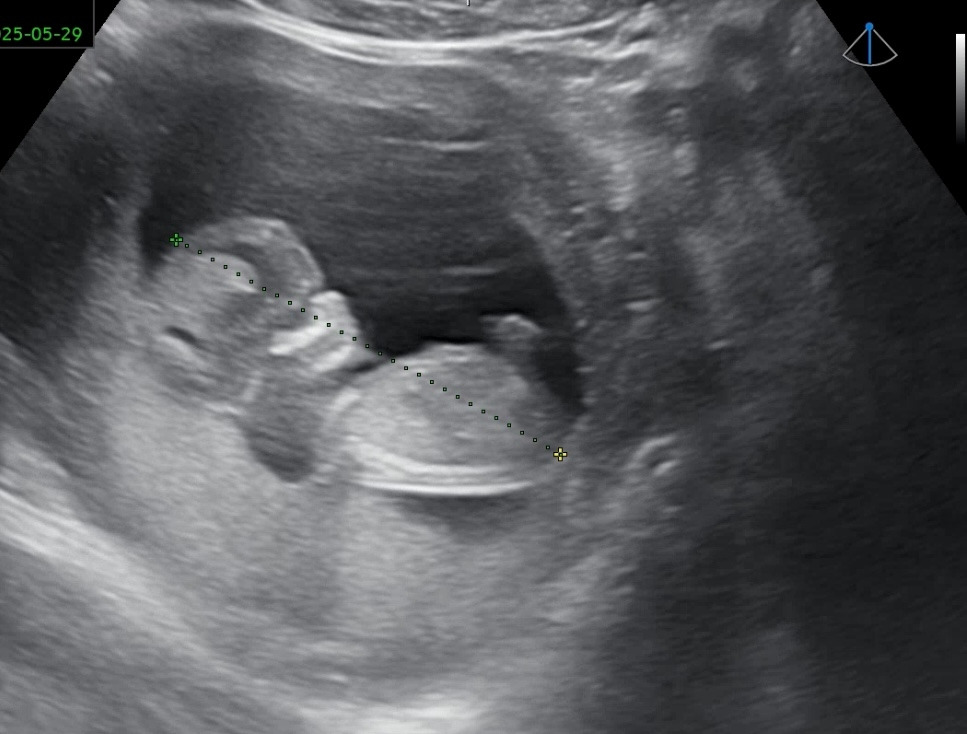

16주차 ㅋㅋㅋ 애기가 좁은지 몸부림을 치고 있다. 너무 귀여워!!!!!! 머리에 두개 점은 눈 아니고 아마 뇌일 텐데.. 꼭 눈같아서 더 웃기다(눈 맞나? ㅋㅋㅋ)